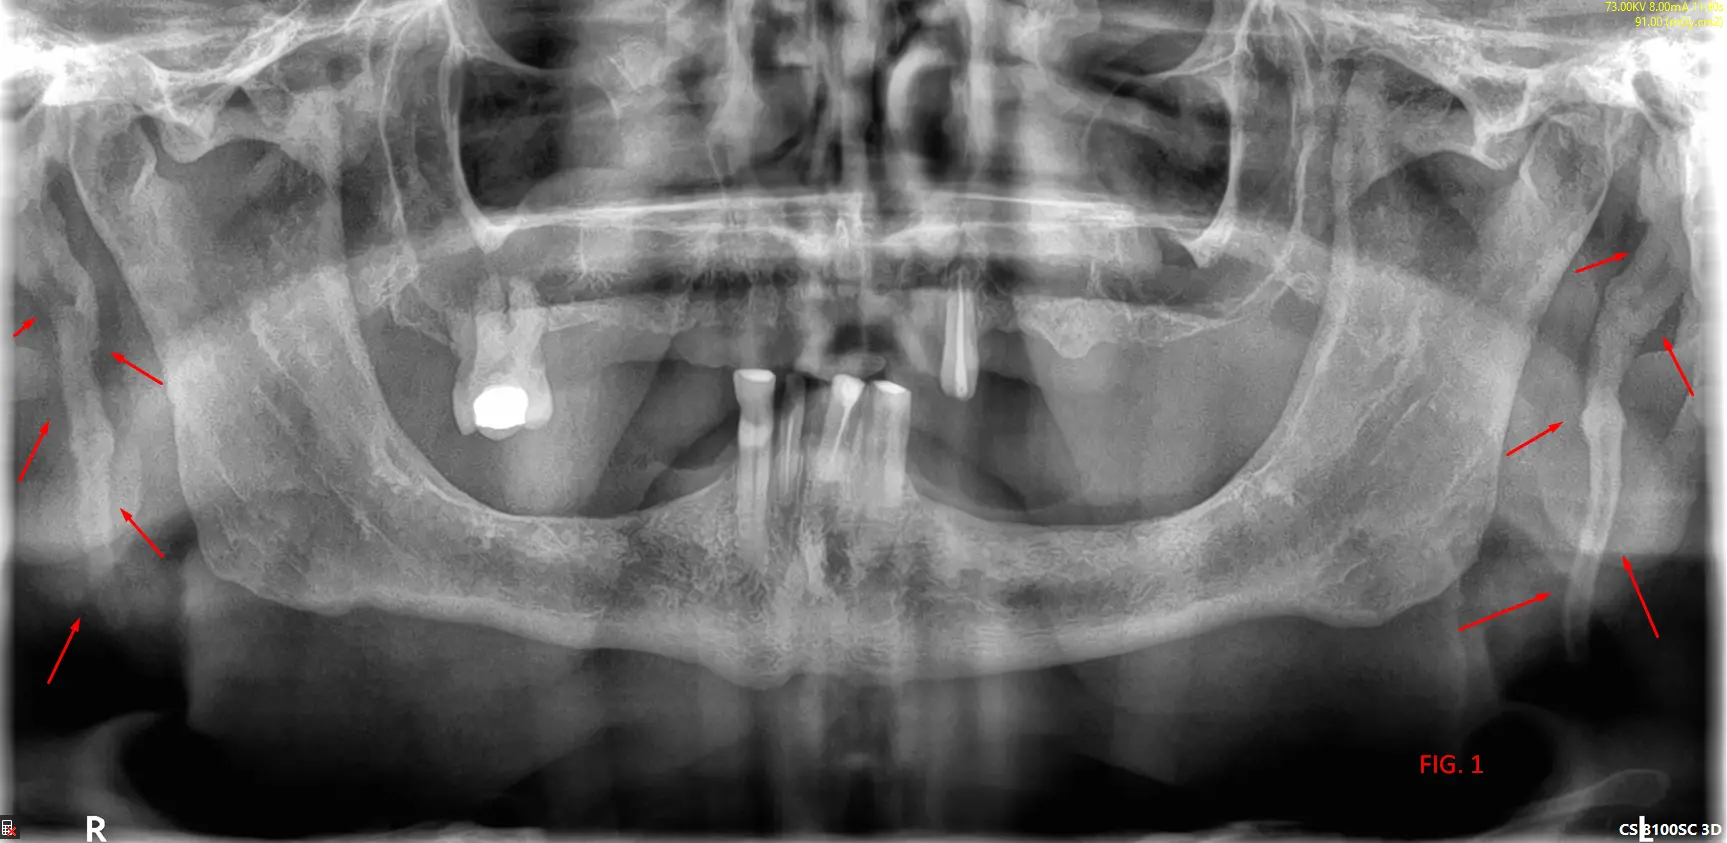

​En el análisis de la ortopantomografía, se identifican estructuras radiopacas bilaterales de morfología alargada. Estas formaciones se extienden desde la base del cráneo (apófisis estiloides) con una trayectoria descendente y anterior hacia el hueso hioides (FIG 1, 2 y 3). Basándose en las características imagenológicas, se concluye que se trata de una osificación bilateral del ligamento estilohioideo, un hallazgo que suele presentarse de forma incidental